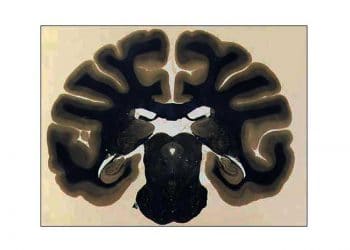

Waterhouse-Friderichsen Sendromu, insanlarda ve septisemik buzağılarda, ateş, böbrek üstü bezinde deride ve müköz zarlarda peteşiyal kanama siyanoz ve peteşiyal kanamalarla...